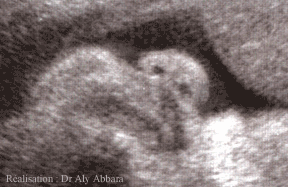

Nez fœtal vu de face